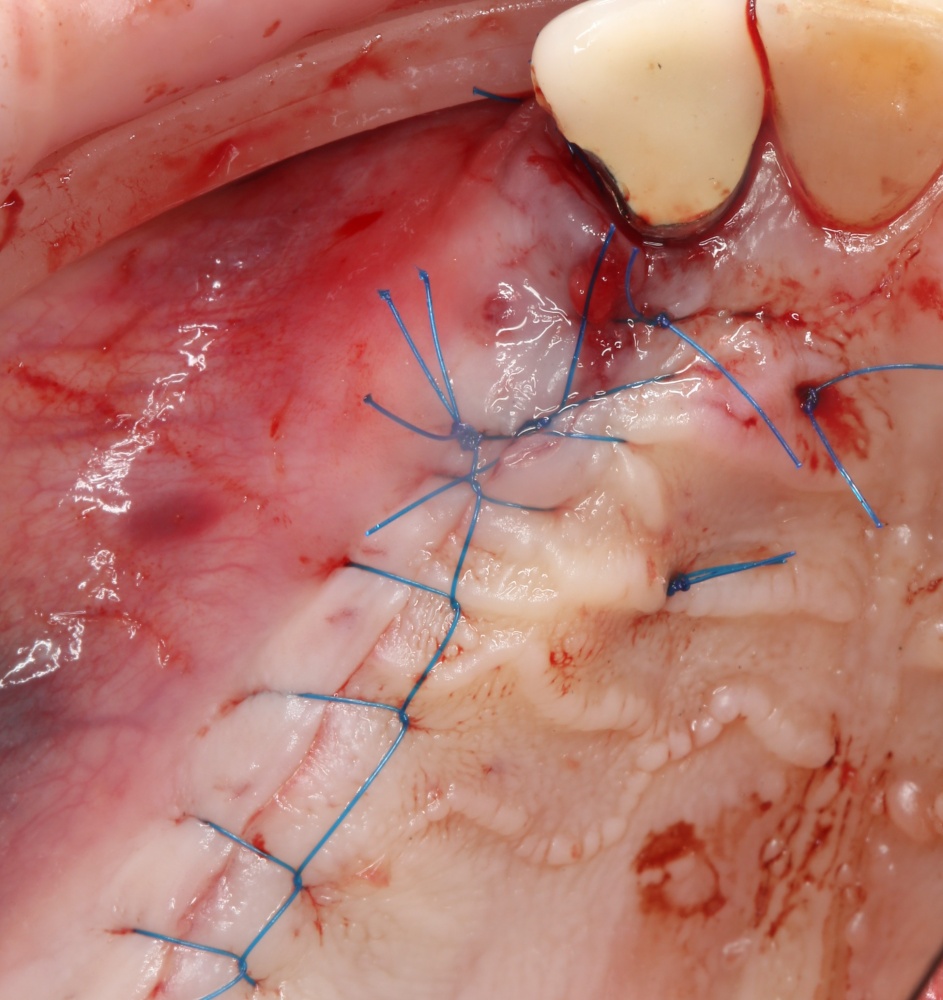

Если на этапе разреза и формирования раны всё сделано правильно, то наложение швов не вызывает особых трудностей. Периостотомия или послабляющие разрезы на периосте не требуются (ни практически никогда не требуются). А сами швы получаются аккуратными и герметичными:

Обрати внимание, что все шовные лигатуры находятся в пределах кератинизированной десны. Это позволяет избежать деформации тканей и лишних рубцов. В наиболее уязвимых местах (около зубов) шовные лигатуры лучше продублировать.

Если бы мне пришлось делать это сейчас, то я бы использовал непрерывный «матрацный» шов. Он удобнее, быстрее в наложении и комфортнее для пациента. Минус — если распускается, то распускается весь. К тому же, его очень неудобно снимать.

Несмотря на то, что уже тогда мы широко использовали непрерывные швы в подобных случаях, здесь я, во-первых, зассал (может распуститься), во-вторых, снятие швов предполагалось в поликлинике по месту жительства пациентки, и мне не хотелось, чтобы там при снятии швов начудили. Как выяснится позже — зря беспокоился.

Неизменно одно — в таких операциях мы использовали и до сих пор используем нерезорбируемые монофиламентные шовные материалы, поскольку они наиболее гигиеничные. Чтобы острые концы нитей не беспокоили пациента, их можно оплавить нагретой гладилкой или гуттаперчевым плаггером.